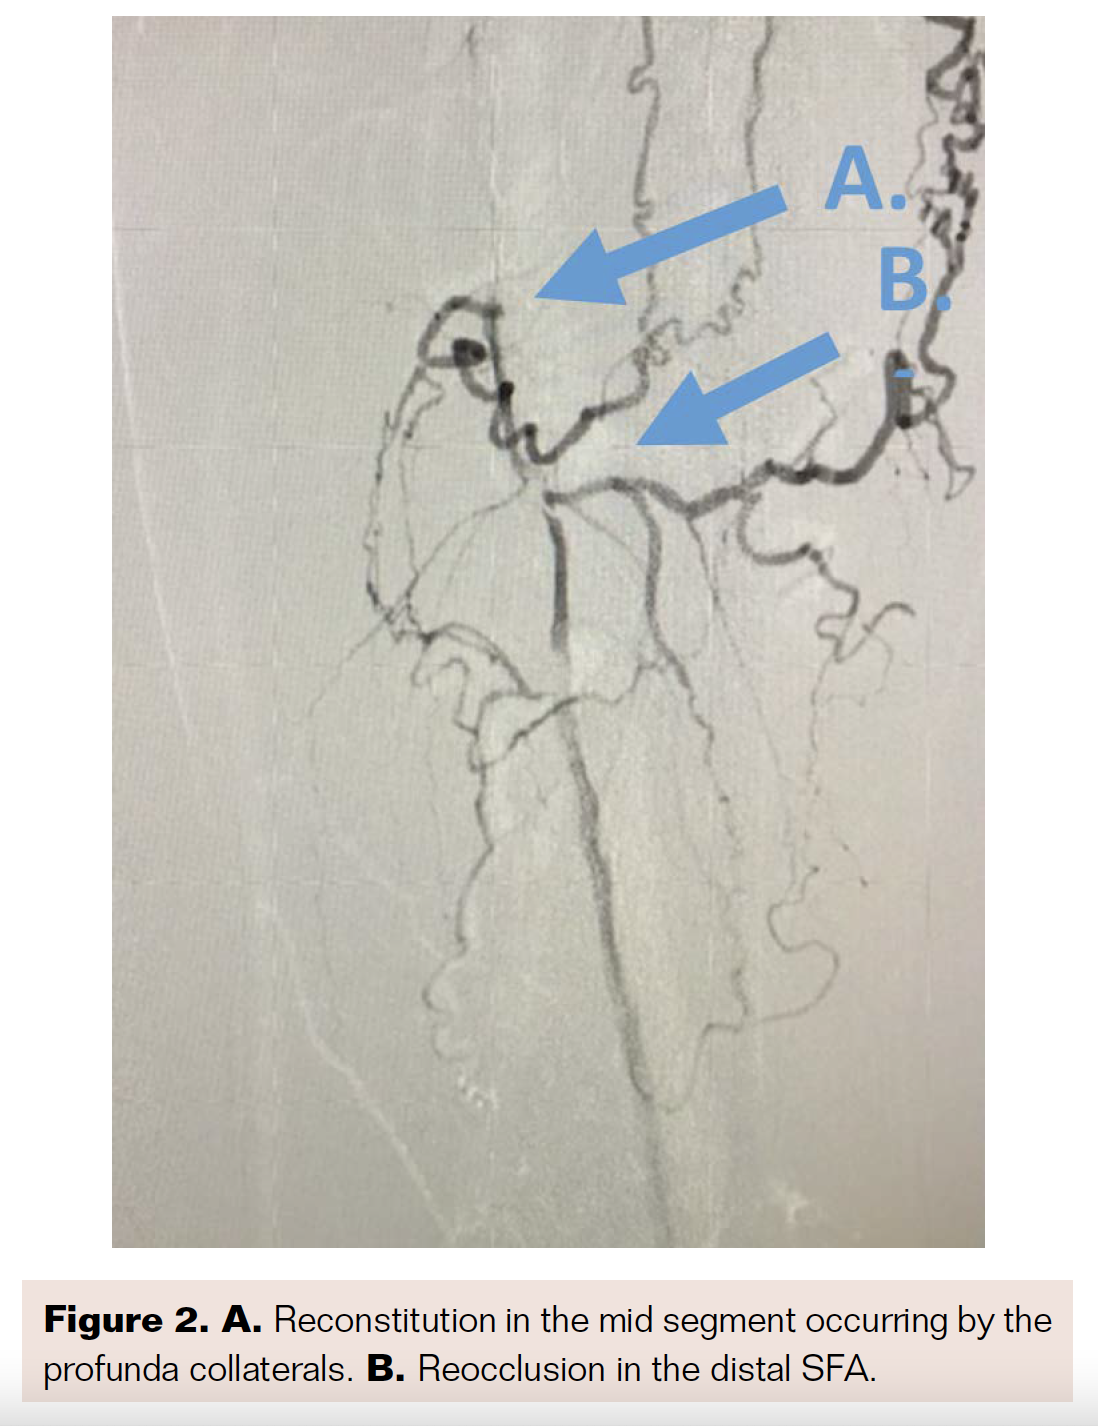

Angiography revealed that the superficial femoral artery (SFA) was occluded in the proximal segment with a short nub (Figure 1) and reconstituted in the mid segment by the profunda collaterals (Figure 2), before becoming reoccluded shortly thereafter and reconstituting in the distal SFA by the profunda collaterals (Figure 3). The P1 and P2 segments of the popliteal artery were patent, but the P3 segment had a short occlusion. The posterior tibial artery and peroneal artery also were patent.